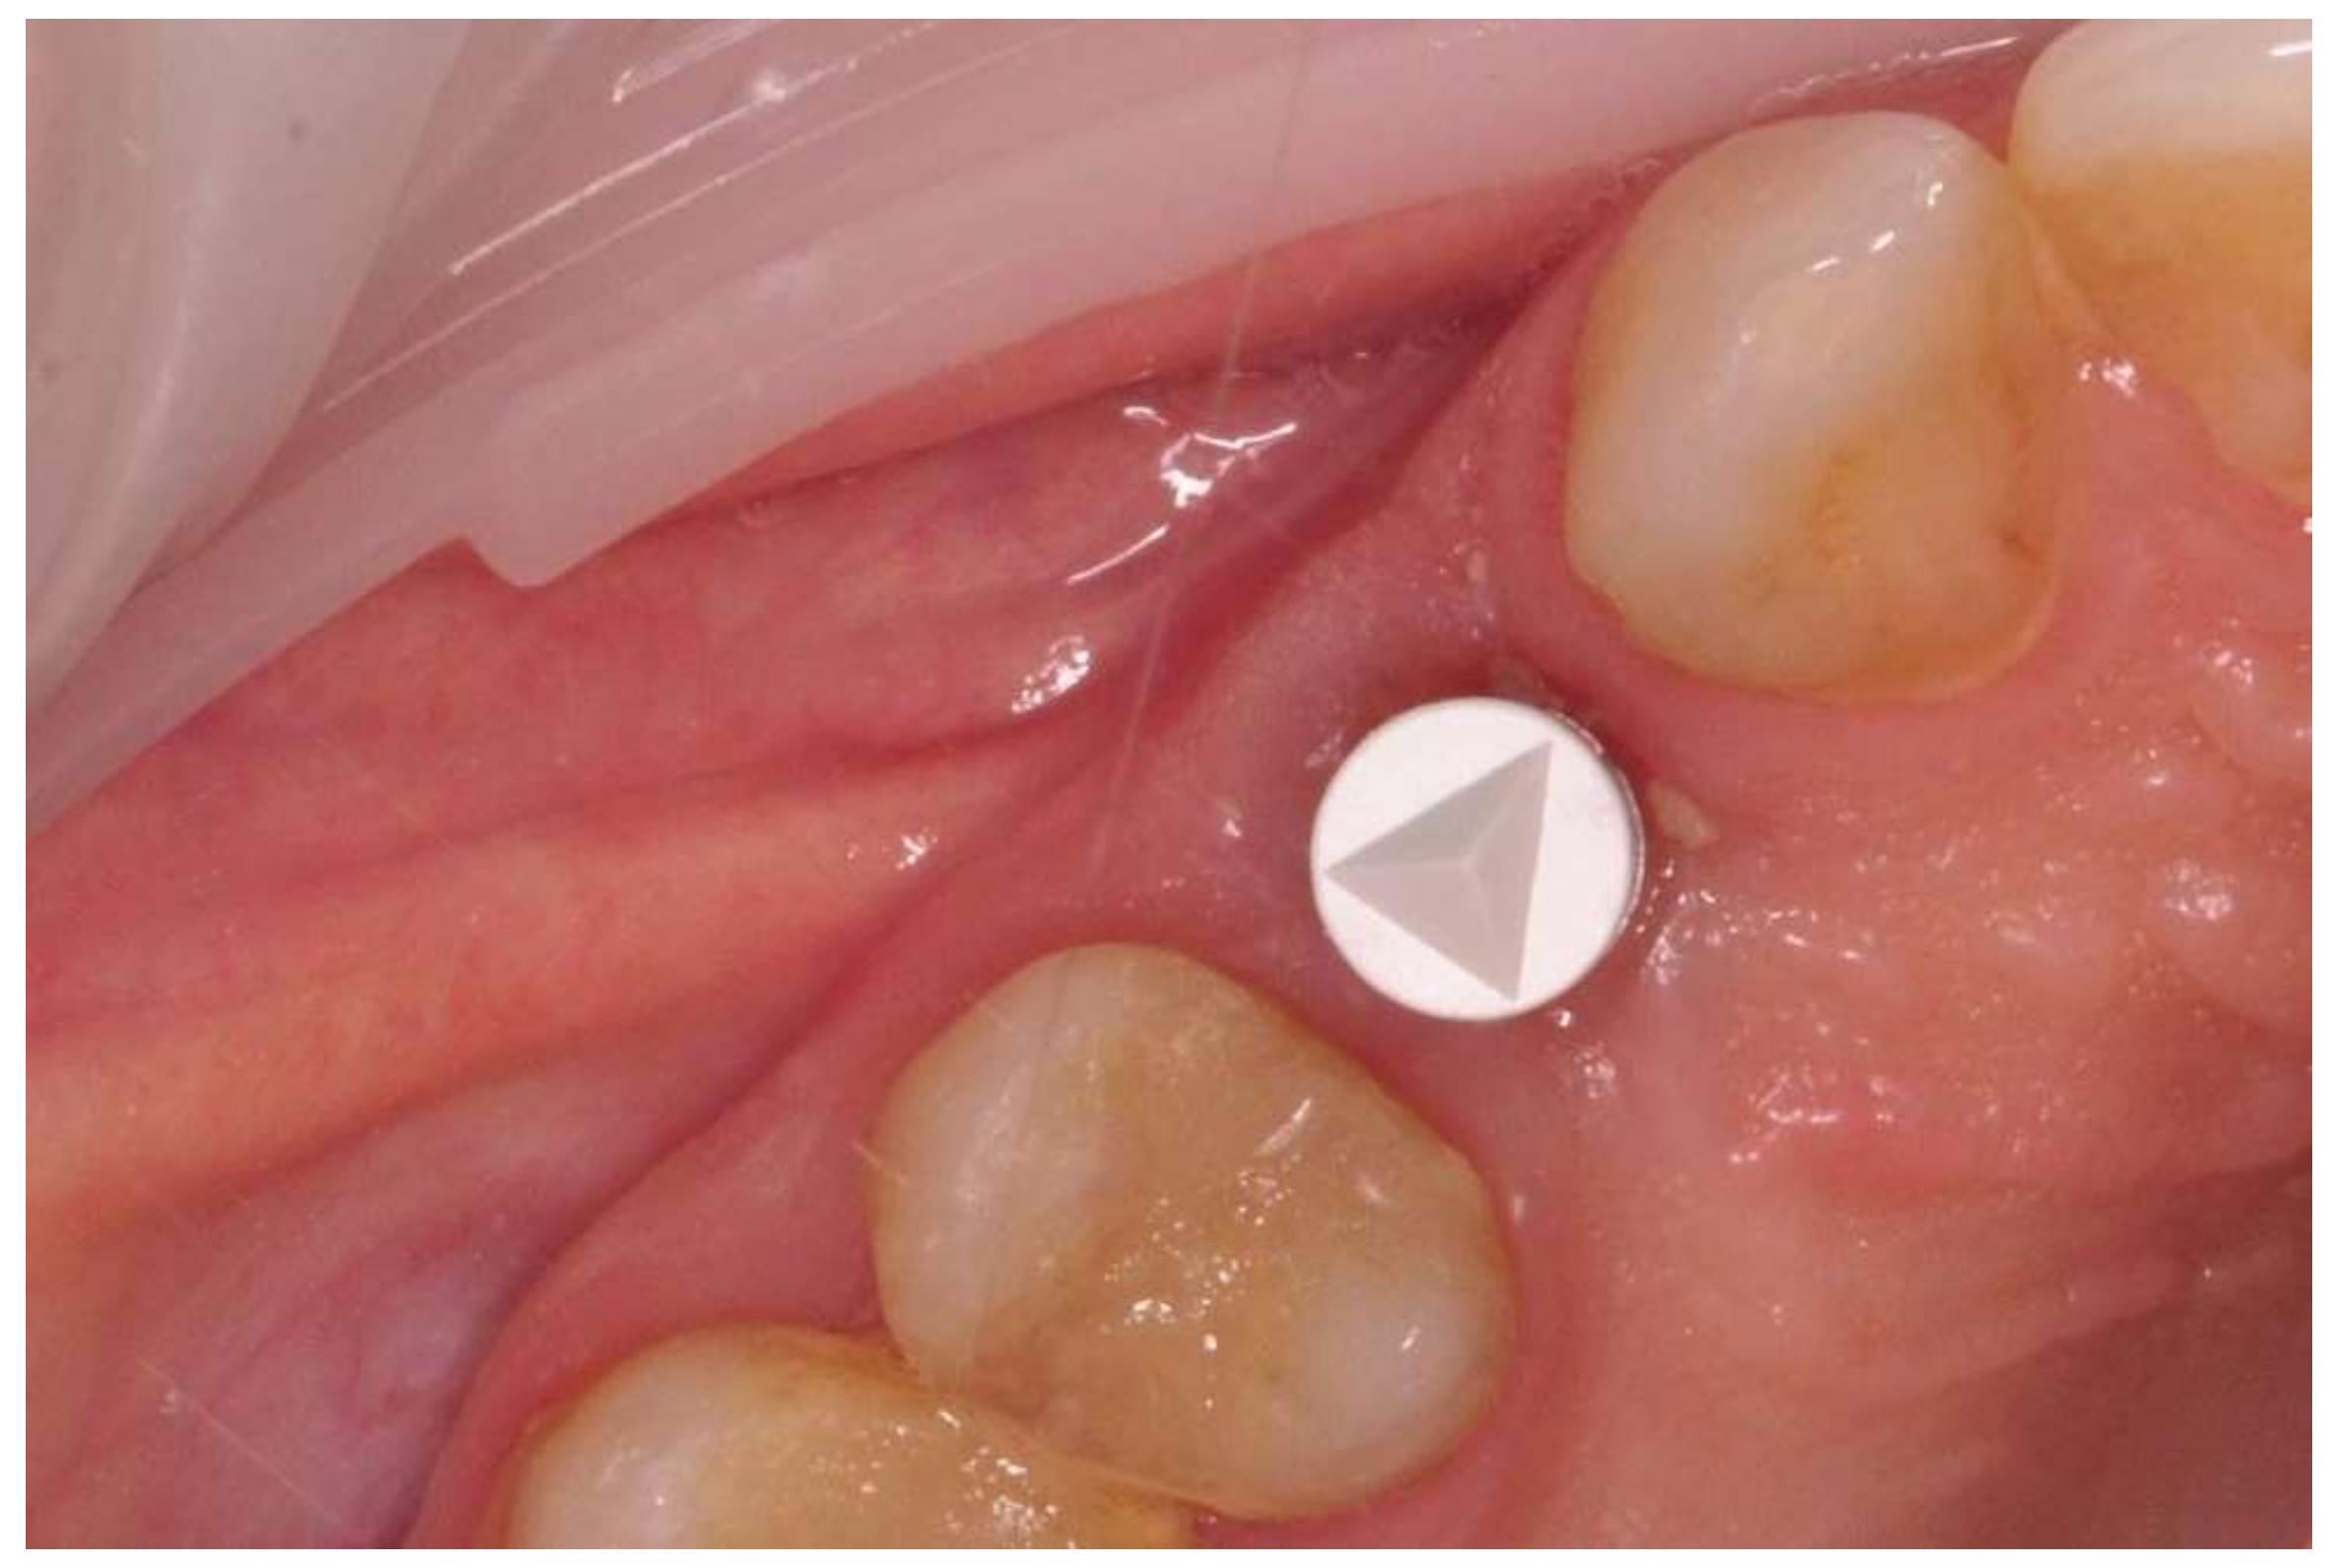

The prosthetic restoration stage started 4 weeks after the implant placement surgery and was prepared in the chairside laboratory by W.G. Patients with no signs of inflammation in the direct vicinity of the implant and with an ISQ (implant’s stability quotient) value of 65 or greater were allowed to participate in the prosthetic protocol. The measurements using the aforementioned device were performed three times in the mesiodistal, buccal and palatal, as well as periapical direction, and the smallest value was considered the cut-off point. Screw-retained implant crowns made of lithium disilicate glass-ceramics, IPS e max CAD LT (Ivoclar Vivadent AG, Schaan, Liechtenstein), were used as the prosthetic restoration materials. After the removal of the healing abutment, the implant bed was cleaned. The scans were taken with an intraoral scanner Sirona Cerec AC Bluecam (DentsplySirona, York, PA, USA) (Figure 2). Subsequently, the crown internal surface was etched and then fixed using Multilink Hybrid Abutment cement (Ivoclar Vivadent AG, Schaan, Liechtenstein) on the previously sandblasted titanium base (TiBase) for Sirona Cerec (DentsplySirona, York, PA, USA). The crown was then screwed onto the implant with a force of 25 Ncm. The occluding relations were controlled using articulating paper (Bausch®, Cologne, Germany) with a thickness of 200, 80, and 8 μm. The hole was filled in with Gradia composite (GC Corporation, Tokyo, Japan) and an RVG image was taken (Figure 3). The patients were instructed on proper hygiene around the dental implant.

Figure 3. Implant loaded with the screw-retained crown.